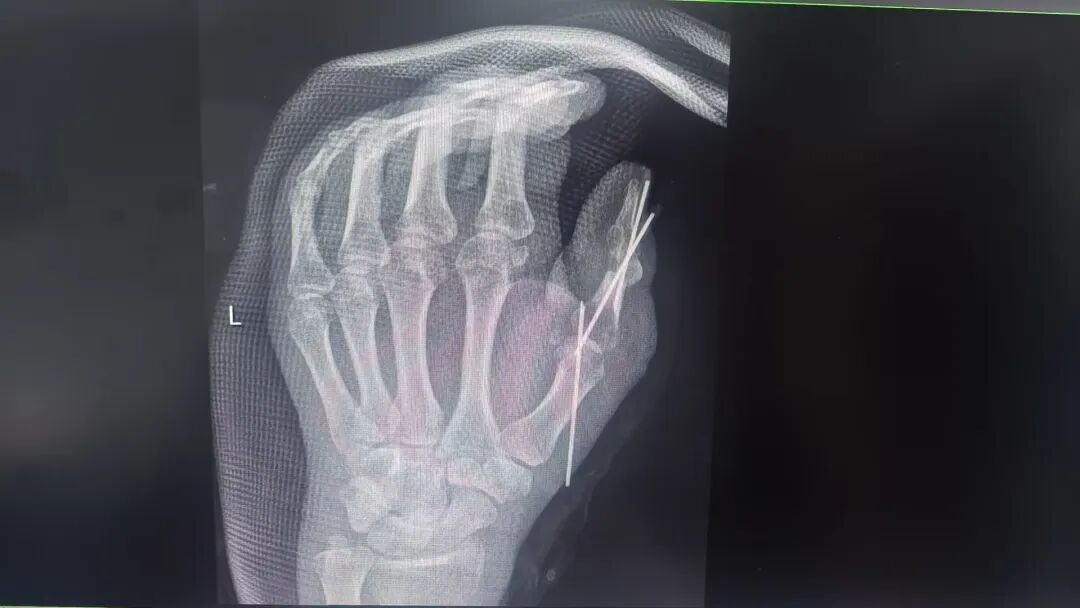

在陈孝均主任的主持下,黄宇医生、向炜医生等针对李先生拇指背侧皮肤软组织缺损情况,对供区选择进行了讨论。本则手足同源及美观原则,最终制定了“游离足附外侧皮瓣修复左手拇指创面”。术中对李先生左手拇指骨折进行了翻修固定+移植掌长肌腱重建左手拇指屈伸肌腱。手术十分成功!

向炜医生回忆术中情况也满是挑战:骨折固定位置奇特,伤口缝线粗大无比!此外不仅伤口感染重,坏死组织多,而且屈伸肌腱未修复,屈肌腱回缩未见,伸肌腱砸伤毁损;桡侧血管神经未修复;整个拇指仅靠尺侧指动脉及少许皮肤软组织相连,危在旦夕!